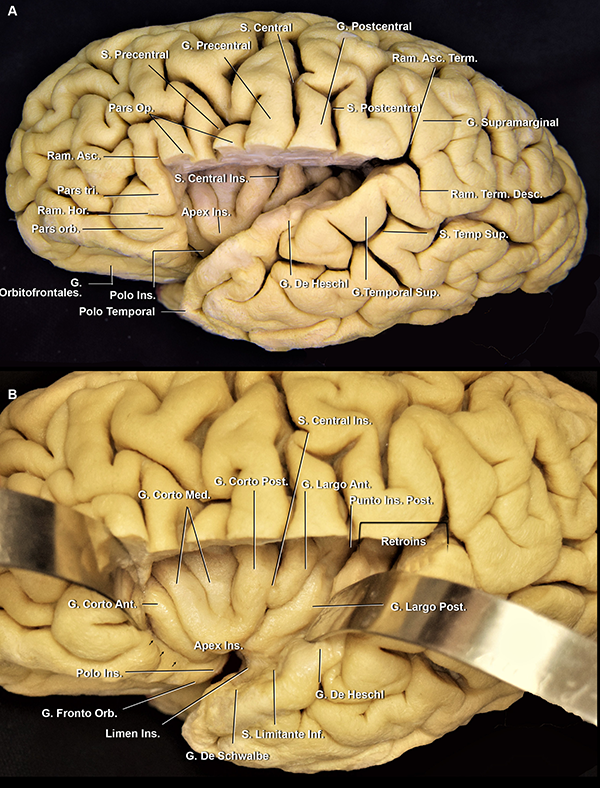

Figura 4: A. Vista latero inferior de un opérculo frontoparietal derecho. El opérculo temporal, la parte lateral del giro orbitario posterior y la parte posterior del giro orbitario lateral fueron removidas. Cuando el surco central no alcanza a la FS, el giro subcentral es visible en la cara lateral cerebral. En cambio, cuando sí lo hace, como en este caso, este giro se localiza en la profundidad de la fisura. Se observa cómo el ramo horizontal se continúa medialmente con el surco limitante anterior. El ápex insular se localiza superior y posteriormente al polo insular. B. Vista lateral del mismo espécimen. C. Vista de la superficie lateral de la ínsula de otro espécimen. Estrella azul: punto insular anterior. Estrella verde: punto insular posterior. S: surco; G: giro; Ant: anterior; Post: posterior; Op: opercularis; Ram: ramo; Hor: horizontal; Orb: orbitario; Ins: insular

El techo de la fisura silviana está conformado por los lóbulos frontal y parietal. La palabra operculum proviene del latín y significa “cortina”:21 los lóbulos frontal, parietal y temporal cubren armónicamente a la cisterna silviana e ínsula (Figura 5A).

El giro frontal inferior se divide por los ramos superficiales de la FS, de anterior a posterior, en la pars orbitalis, la triangularis y la opercularis (Figura 3 y 5A).

La pars orbitalis se continua basalmente con los giros orbitarios lateral y posterior. Es el área más prominente del giro frontal inferior (Figura 5A y 9A)22 y se relaciona superficialmente con el keyhole (agujero de trépano llave) del abordaje pterional.

La pars triangularis, que posee una forma de “V”,22,23 suele albergar un ramo originado del surco frontal inferior y cubre al ápex insular. Por otro lado, la pars opercularis, que tiene forma de “U”,22 alberga un ramo originado del surco precentral, o en su defecto, al extremo inferior del surco precentral (Figura 3 y 5). La pars opercularis, se recuesta superficialmente sobre el giro corto posterior de la ínsula (Figura 4A). Más aún, la rodilla de la cápsula interna y el foramen de Monro se ubican en la profundidad de dicho giro corto (Figura 12B). Finalmente, el área de Broca del lenguaje, se compone de la pars triangularis y opercularis del hemisferio dominante.22

Piso: opérculo temporal

La parte opercular del giro temporal superior está dividida en dos: anteriormente, el plano polar o planum polare, y posteriormente, el plano temporal o planum temporale. La estructura neural que marca esta división es el giro transverso anterior o, simplemente, giro de Heschl. Este es el giro más voluminoso del opérculo temporal, tiene una orientación diagonal y su extremo posteromedial apunto hacia el brazo posterior de la cápsula interna, el núcleo pulvinar del tálamo y el atrio (Figura 12A, B, D).15,22

El plano polar es un área integrada por giros cortos oblicuos menores: los giros de Schwalbe (Figura 6B).25 Por un lado, tiene una orientación lateromedial en el eje axial, escondiendo su punta anterior debajo del giro orbitario posterior (Figura 6).15 Por otro lado, tiene una orientación oblicua inferior en el eje coronal, que contribuye al agrandamiento del espacio subaracnoideo en el punto silviano anterior.22,23

El plano temporal está compuesto por dos o tres giros transversos. Es un área de forma triangular cuyo ápex apunta hacia el atrio ventricular. El giro de Heschl y la parte posterior del giro temporal superior constituyen el área auditiva primaria (Figura 6A, 10A y B).22 En su extremo anterolateral, el giro de Heschl se encuentra en el mismo plano coronal que el giro postcentral. Además, se evidenció que el giro de Heschl a su vez se encuentra en el mismo plano que el conducto auditivo externo (CAE) (Figura 5). En el plano coronal, tiene una orientación horizontal, haciendo que la disección de la fisura en esta área sea más dificultosa.